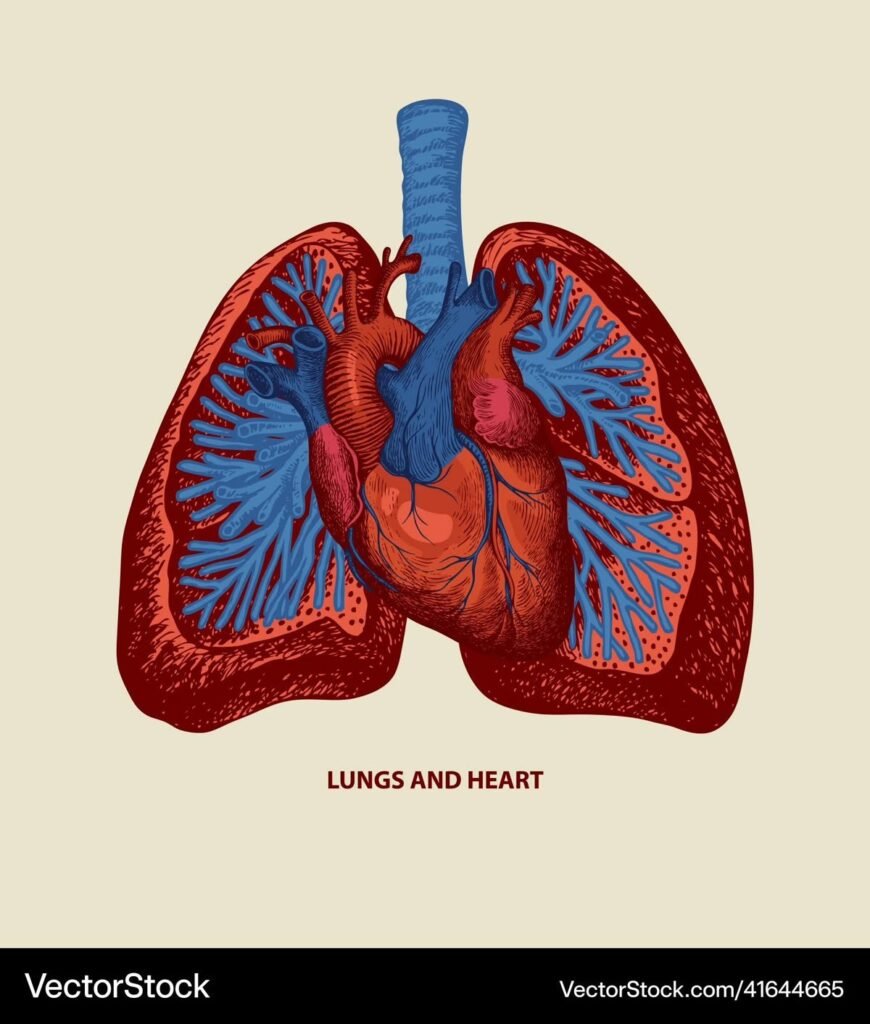

Heart & Lung Transplantation

Heart and lung transplantation can be a life-saving option when medicines and other treatments no longer work. With timely referral and expert care, it can greatly improve survival and quality of life.